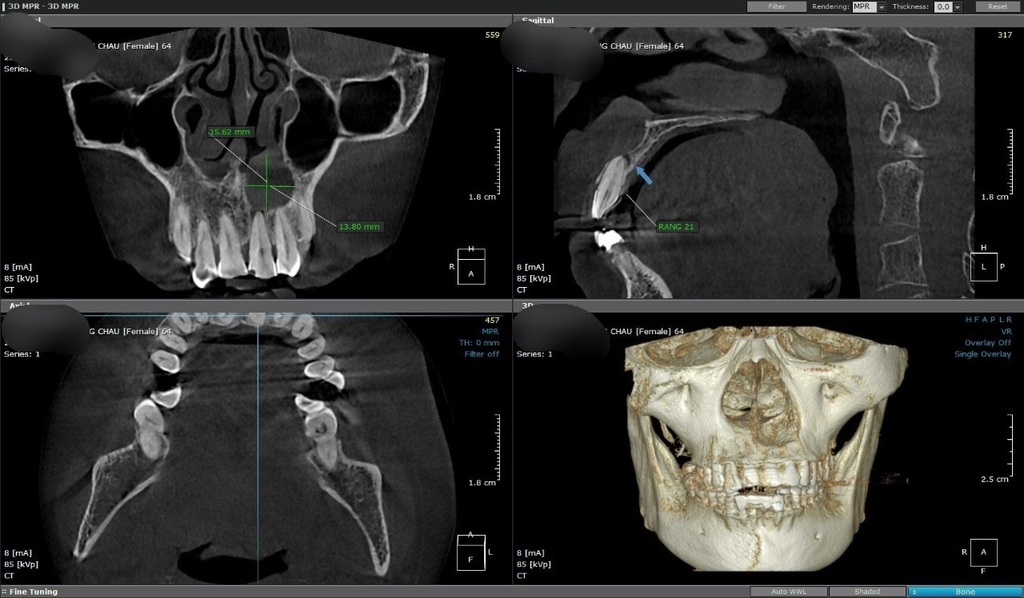

Chụp CT răng là phương pháp cận lâm sàng hỗ trợ giúp bác sĩ chẩn đoán chính xác và có phương án điều trị tối ưu nhất. Vai trò của chụp CT răng:

• Xác định được mật độ xương hàm.

• Chẩn đoán chính xác các bệnh lý răng miệng như: sâu răng, nha chu, viêm tủy,…. Từ đó xác định được mức độ nghiêm trọng để có biện pháp can thiệp kịp thời. Thông thường, các bệnh lý này rất phổ biến nhưng ít được phát hiện và chữa trị sớm.

• Phát hiện các tổn thương nặng ở vùng xương hàm như: Viêm nhiễm,tiêu xương ổ răng u, nang hoặc khi bị chấn thương nặng.

• Xác định được hình thái của răng hoặc răng mọc lệch để điều chỉnh kịp thời. Từ đó tránh các tổn thương và phục hồi thẩm mỹ cho răng miệng.

• Quan sát, theo dõi quá trình thay răng ở trẻ em.

• Khi thực hiện các dịch vụ thẩm mỹ như: Niềng răng, bọc răng, thay răng,… chụp CT răng cũng được chỉ định để thuận tiện cho việc quan sát và điều chỉnh các thủ thuật của bác sĩ khi thực hiện cho khách hàng.